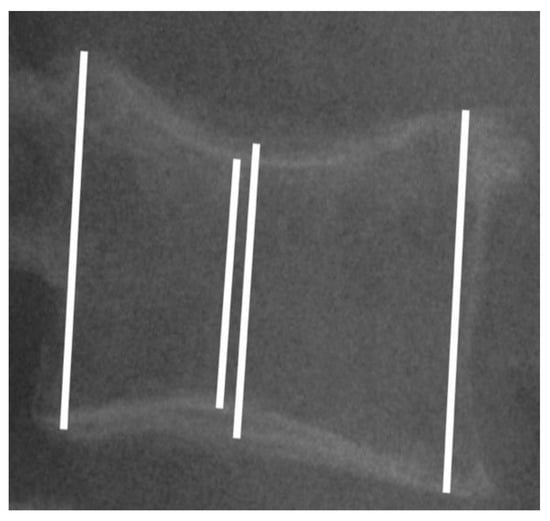

All of the patients were studied pre-surgery, pre-cementation, post-cementation, at the first medical check-up (6 weeks post-surgery) and at the last medical check-up (minimum 6 months). A lateral X-ray was used to take the measurements. All of the images were taken at a distance of one meter from the patients, ensuring that the upper and lower plate were properly aligned. In each vertebral body, the anterior, middle (most collapsed zone and least collapsed zone) and posterior edge heights were measured (Figure 1). The vertebral height was the average of each part of the vertebral body. In each period, the difference was calculated from the preoperative values. The posterior edge of one adjacent nonfractured vertebral body was also measured in each study period to validate the measurements. The first and second authors made the measurements using a digital PACS caliper, and they were blinded to clinical context in each case.

Figure 1.

Lateral X-ray showing the measurements performed in the anterior, middle (most collapsed zone and least collapsed zone) and posterior edges. Vertebral height was the average of each part of the vertebral body.